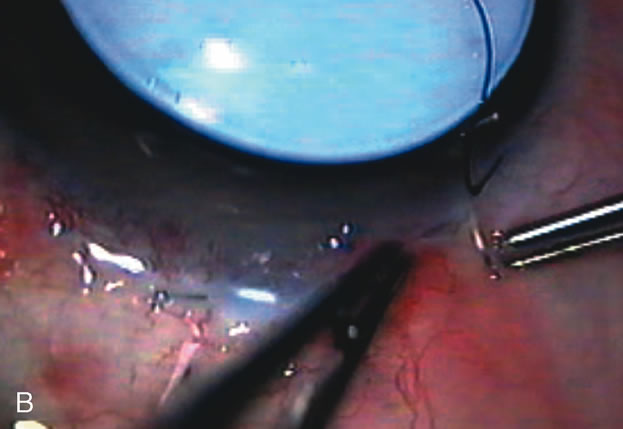

In years past, patients with both cataract and glaucoma frequently provided overwhelming surgical challenges for the ophthalmologist. The ability to carry out phacoemulsification through a 3.2-mm corneal incision along with inserting a foldable IOL is a vast improvement over 11-mm incisions that were common a decade ago (Fig. 1). The anatomical and inflammatory changes to the eye are less with small incision techniques, improving the likelihood of success with concomitant glaucoma surgery. Pharmacologic inhibition of fibrosis along with postoperative wound revision increases the long-term success rate of filtration surgery when combined with lens extraction. (Fig. 2). The learning curve may be steep at times, but the blending of cataract and glaucoma surgical skills slowly falls into place as the surgeon constantly learns and upgrades his or her technique.

Fig. 1. The anatomic advantage of small incision cataract surgery for the glaucoma patient. A. Long-term bleb function with a large cataract incision is difficult to achieve with either ECCE-trabeculectomy or trabeculectomy followed later by ECCE. This bleb failed to form sufficiently when combined with large incision ECCE. The inflammation, bleeding, and long-term wound healing with stimulation of fibroblasts associated with this technique are more likely to cause bleb failure. In addition, the increased iris manipulation necessary to deliver the nucleus and subsequent iris repair adds to the long-term breakdown of the blood aqueous barrier. B and C. Two-site phacotrabeculectomy has the advantage of small incision cataract surgery combined with separate site trabeculectomy. The incision size is one third the size of the standard ECCE. The inflammation is less severe, and cataract wound healing is confined to the temporal area. Visual rehabilitation with phacoemulsification and foldable IOL is much faster. Phacoemulsification allows successful lens extraction even in the unfriendly environment of a smaller pupil compared with ECCE. The trabeculectomy is performed in an entirely different site, well away from the wound healing associated with temporal phacoemulsification. The likelihood of this filter functioning long-term is greater than with ECCE-trabeculectomy. D. The surgeon also has the option of single-site phacotrabeculectomy with foldable IOL. Both the lens extraction and trabeculectomy are performed through one small 3.5-mm limbal incision.